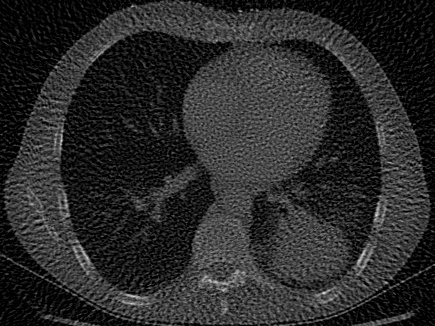

| Computed Tomography (CT) [28] | 2D | X-ray CT scan of a human chest, used to evaluate signal recovery in a classic underdetermined inverse problem. |

In addition to synthetic experiments, we evaluate each model on diverse tasks involving real-world 2D images and 3D volumes. These experiments assess the models’ ability to overfit, generalize, and solve inverse problems with natural signals. We use 10 images from DIV2K [27] to test image overfitting, super-resolution, and denoising at two different levels of Gaussian noise. We use 7 CT scans, including a 2D chest CT scan from Clark et al. [28] and 6 CT scans from the Generalizable Dose Prediction for Heterogeneous Multi-Cohort and Multi-Site Radiotherapy Planning challenge at AAPM 2025 [31], to evaluate performance in a classic underdetermined inverse problem, in which the task is to recover an image from undersampled X-ray projections. We evaluate volumetric performance using the occupancy function and surface of the 3D Stanford Dragon [29]. On both of these 3D signals we test both volume overfitting and super-resolution. Our real-data signals and tasks are summarized in the bottom half of Table˜1, with further details provided in Section˜5.4.

Visual and quantitative results for computed tomography, denoising, and super-resolution are presented in Figure˜5 and Figure˜6, respectively. For all of these tasks involving natural 2D signals, we find that the simple Grid baseline with total variation (TV) regularization is optimal across all model sizes. However, on our 3D Dragon occupancy and surface super-resolution tasks, GA-Planes, WIRE, and to some extent SIREN outperform the Grid at the smallest model sizes. As in our overfitting experiments, this suggests that some INRs and hybrid models may be best suited to representing and compressing signals with constant regions and sharp edges characteristic of lower-dimensional structure. Comprehensive visualizations and quantitative metrics including an additional denoising task with are provided in Section˜5.7.

Computed Tomography (CT).

For CT experiments, we train models on a real chest CT slice from the dataset in Clark et al. [28], which was also used in WIRE [16]. The training data was 100 projection measurements of the original 326435 chest CT slice, forming a 100435 sinogram equivalent to approximately 30% of the total pixel count in the original image. Since this inverse problem is inherently underdetermined, we apply TV regularization in our Grid model. The TV hyperparameter was tuned using the classic Shepp-Logan phantom image [37] as a reconstruction target.